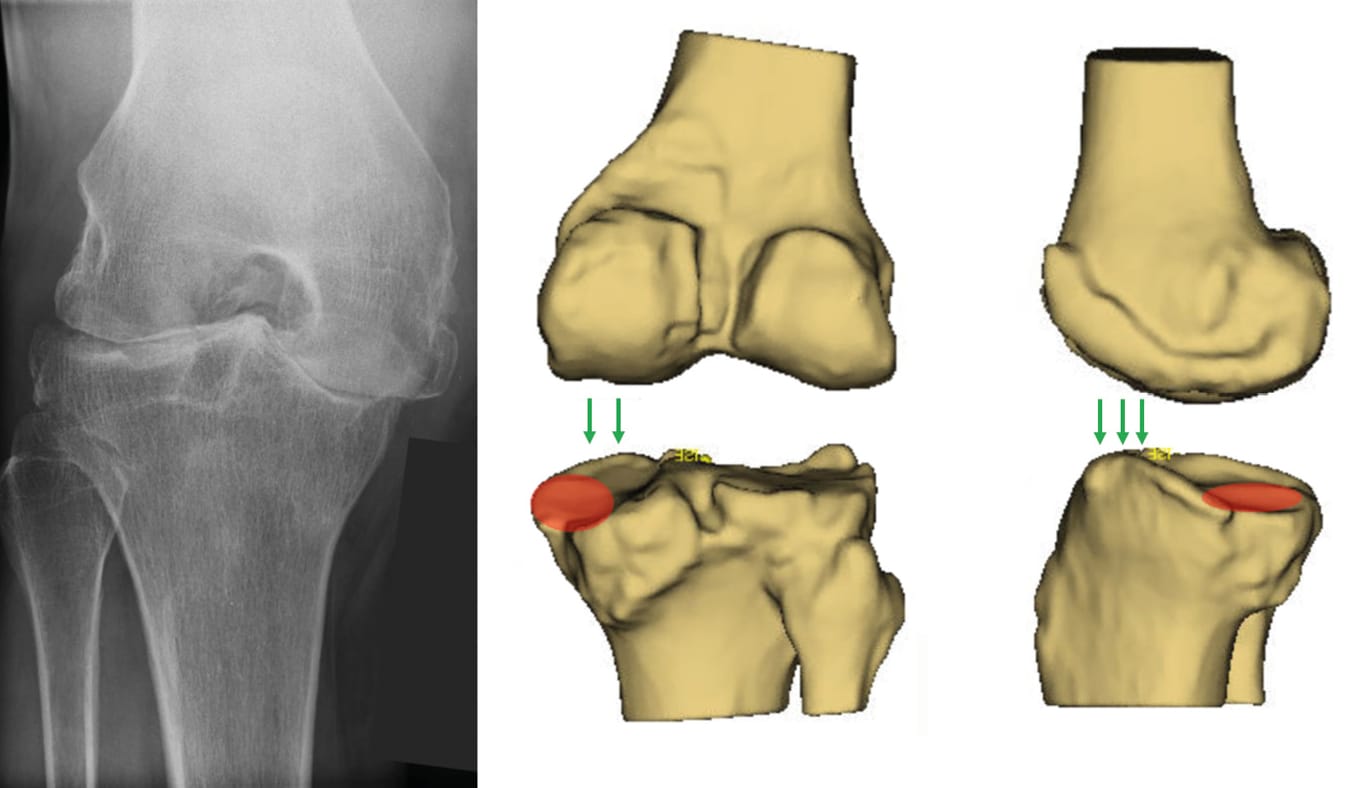

Recent anatomic studies have demonstrated that in healthy knees, phenotypes are highly variable, particularly the joint line orientation [9], Hirschmann MT, Hess S, Behrend H, Amsler F, Leclercq V, Moser LB (2019) Phenotyping of hip-knee-ankle angle in young non-osteoarthritic knees provides better understanding of native alignment variability. Knee Surg Sports Traumatol Arthrosc 27 (5):1378-1384. [10], Hirschmann MT, Khan ZA, Sava MP, von Eisenhart-Rothe R, Graichen H, Vendittoli PA, Riviere C, Chen AF, Leclercq V, Amsler F, Lustig S, Bonnin M (2024) Definition of normal, neutral, deviant and aberrant coronal knee alignment for total knee arthroplasty. Knee Surg Sports Traumatol Arthrosc 32 (2):473-489. [11], Hirschmann MT, Moser LB, Amsler F, Behrend H, Leclercq V, Hess S (2019) Phenotyping the knee in young non-osteoarthritic knees shows a wide distribution of femoral and tibial coronal alignment. Knee Surg Sports Traumatol Arthrosc 27 (5):1385-1393. [12] Hirschmann MT, Moser LB, Amsler F, Behrend H, Leclerq V, Hess S (2019) Functional knee phenotypes: a novel classification for phenotyping the coronal lower limb alignment based on the native alignment in young non-osteoarthritic patients. Knee Surg Sports Traumatol Arthrosc 27 (5):1394-1402. . The trochlear angle, between the distal condylar line and the trochlear axis, is also variable so that the trochlea remains aligned with the quadriceps line of force in the coronal plane whatever the joint line obliquity [13], Howell SM, Sappey-Marinier E, Niesen AE, Nedopil AJ, Hull ML (2023) Better forgotten joint scores when the angle of the prosthetic trochlea is lateral to the quadriceps vector in kinematically aligned total knee arthroplasty. Knee Surg Sports Traumatol Arthrosc 31 (12):5438-5445. [25], Rosa SB, Hazratwala K, Wilkinson MPR (2023) Mismatch between trochlear coronal alignment of arthritic knees and currently available prosthesis: a morphological analysis of 4116 knees and 45 implant designs. Knee Surg Sports Traumatol Arthrosc 31 (8):3116-3123. [28], Sappey-Marinier E, Bini S (2023) Unrestricted kinematic alignment corrects fixed flexion contracture in robotically aligned total knees without raising the joint line in extension. J Exp Orthop 10 (1):114. [29] Sappey-Marinier E, Howell SM, Nedopil AJ, Hull ML (2022) The Trochlear Groove of a Femoral Component Designed for Kinematic Alignment Is Lateral to the Quadriceps Line of Force and Better Laterally Covers the Anterior Femoral Resection Than a Mechanical Alignment Design. J Pers Med 12 (10). . With kinematic alignment, or any kind of individualized alignment, surgeons aim to restore the native phenotype and align the implants with the joint line: they prioritize coronal limb alignment, sometimes to the detriment of trochlear orientation, to an extent that the patellofemoral joint becomes a mere subordinate of the tibiofemoral joint. In most off-the-shelf (OTS) TKA, the orientation of the prosthetic trochlea is set at 6° to 7° valgus from the prosthetic distal condylar line (Prosthetic Trochlear Angle) [6], Dejour D, Ntagiopoulos PG, Saffarini M (2014) Evidence of trochlear dysplasia in femoral component designs. Knee Surg Sports Traumatol Arthrosc 22 (11):2599-2607. [20], Müller JH, Li K, Reina N, Telmon N, Saffarini M, Cavaignac E (2020) Sexual and ethnic polymorphism result in considerable mismatch between native trochlear geometry and off-the-shelf TKA prostheses. Knee Surg Sports Traumatol Arthrosc 28 (12):3871-3878. [25], Rosa SB, Hazratwala K, Wilkinson MPR (2023) Mismatch between trochlear coronal alignment of arthritic knees and currently available prosthesis: a morphological analysis of 4116 knees and 45 implant designs. Knee Surg Sports Traumatol Arthrosc 31 (8):3116-3123. [26] Saffarini M, Demey G, Nover L, Dejour D (2016) Evolution of trochlear compartment geometry in total knee arthroplasty. Ann Transl Med 4 (1):7. . Consequently, when using such an implant with kinematic alignment, the trochlear orientation becomes variable and can deviate medially or laterally from the quadriceps line of force (Figure 5) [28], Sappey-Marinier E, Bini S (2023) Unrestricted kinematic alignment corrects fixed flexion contracture in robotically aligned total knees without raising the joint line in extension. J Exp Orthop 10 (1):114. [29] Sappey-Marinier E, Howell SM, Nedopil AJ, Hull ML (2022) The Trochlear Groove of a Femoral Component Designed for Kinematic Alignment Is Lateral to the Quadriceps Line of Force and Better Laterally Covers the Anterior Femoral Resection Than a Mechanical Alignment Design. J Pers Med 12 (10). .

With individualized implants, all areas are designed independently, and the trochlear groove can be oriented to optimize patellofemoral kinematics independently from the femoral condyles, which should be aligned to optimize tibiofemoral kinematics [17], Kuo AW, Chen DB, Wood J, MacDessi SJ (2020) Modern total knee arthroplasty designs do not reliably replicate anterior femoral morphology. Knee Surg Sports Traumatol Arthrosc 28 (9):2808-2815. [20], Müller JH, Li K, Reina N, Telmon N, Saffarini M, Cavaignac E (2020) Sexual and ethnic polymorphism result in considerable mismatch between native trochlear geometry and off-the-shelf TKA prostheses. Knee Surg Sports Traumatol Arthrosc 28 (12):3871-3878. [23], Rivière C, Iranpour F, Harris S, Auvinet E, Aframian A, Parratte S, Cobb J (2018) Differences in trochlear parameters between native and prosthetic kinematically or mechanically aligned knees. Orthop Traumatol Surg Res 104 (2):165-170. [24] Rivière C, Vigdorchik JM, Vendittoli PA (2019) Mechanical alignment: The end of an era! Orthop Traumatol Surg Res 105 (7):1223-1226. . This decoupling of the patellofemoral and tibiofemoral joints solves the trochlear dilemma of kinematic alignment with off-the-shelf implants [27] Saffarini M, Hirschmann MT, Bonnin M (2023) Personalisation and customisation in total knee arthroplasty: the paradox of custom knee implants. Knee Surg Sports Traumatol Arthrosc 31 (4):1193-1195. (Figure 6).